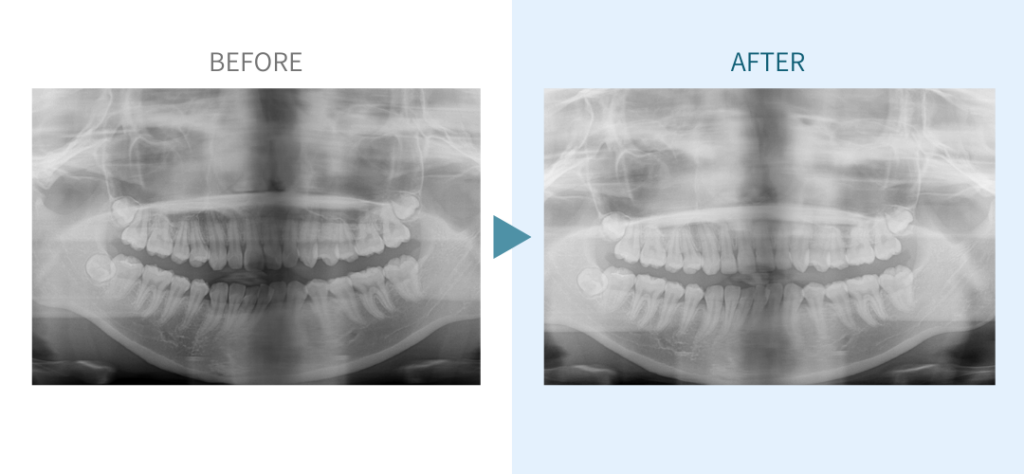

デンタルチームジャパンでは、サイナスリフト(上顎洞底挙上術)や骨造成など、他院で「骨が足りない」と断られた難症例にも対応しています。

こちらではその一部の症例についてご紹介します。